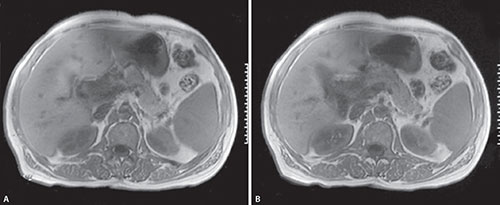

Nephrographic Phase

Nephrographic phase is considered as the optimum phase for not only detection but also characterization of renal masses. In this phase, there is a homogeneous enhancement of both the cortex and medulla. This phase is useful particularly for the lesions <;3 cm.55 Any enhancement>20 HU is considered suggestive of malignancy and this lesion enhancement is usually best visualized on the NP.56 Renal infarction, traumatic parenchymal lesions, and acute pyelonephritis is also best visualized on the NP as the lesions stand out as hypodense areas against the enhanced renal parenchyma (Figs. 18A and B).